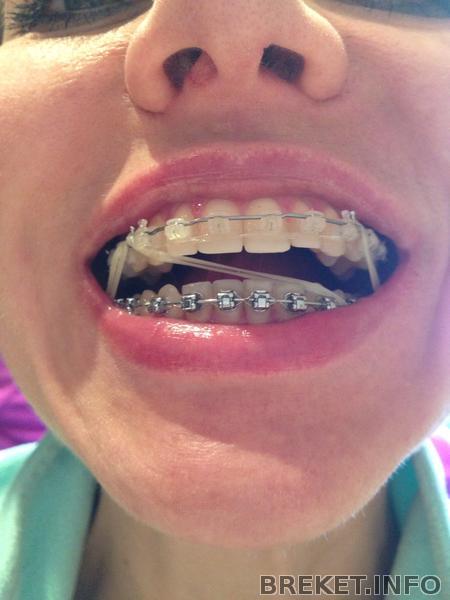

Тем временем клыки совсем придвинулись к пятеркам, а улыбка в данный момент выглядит, мягко говоря, отвратительно

и Бог с ними с щелями, но верхние зубы опускаются все ниже, уже совсем закрывают нижние - из-за чего, когда я улыбаюсь, очень сильно видно десну, что уж говорить о том, когда смеюсь((( Начала снова ненавидеть свои фотографии из-за этого и вообще в полном расстройстве